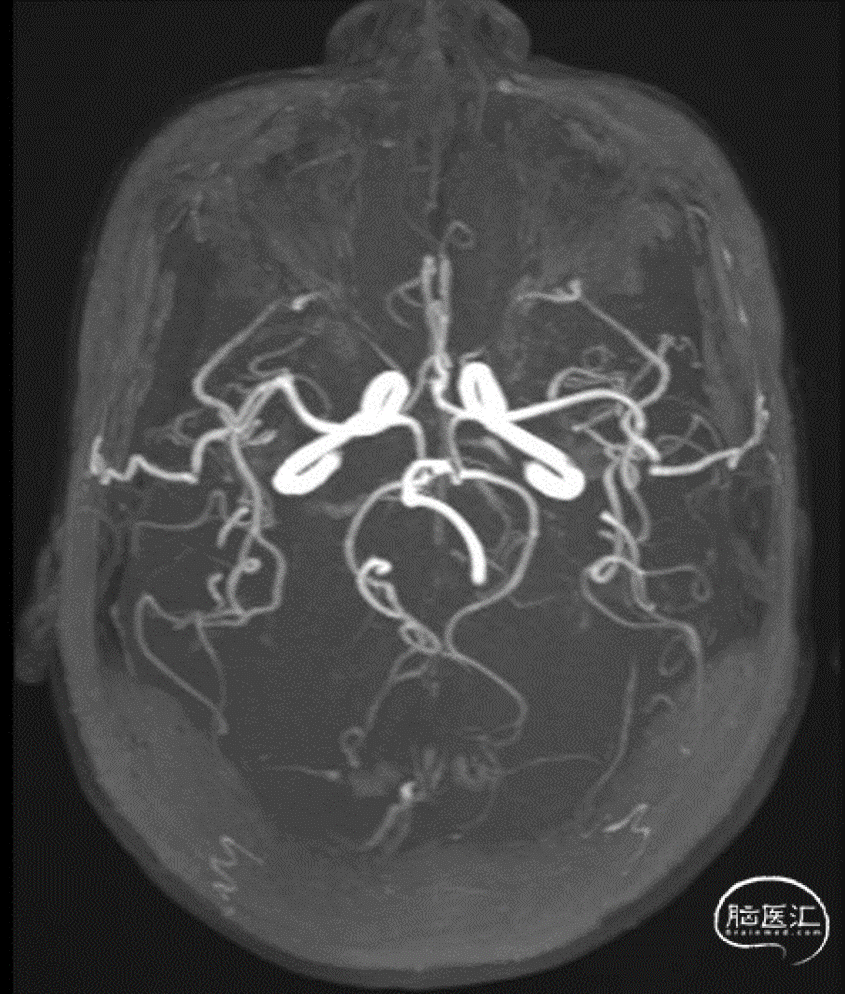

术前造影:右侧大脑中动脉M1远端不显影,断端整齐。

将6F长鞘放置至右侧颈内动脉起始段,随后成功置入微导丝和微导管至血栓远端。在微导管的支撑下将React™ 71远端通路导管送至右侧大脑中动脉血栓近端。

React™ 71远端通路导管到位后行持续负压抽吸。抽吸后造影提示:右侧大脑中动脉血管成功再通。

术后DSA:

右侧大脑中动脉再通,mTICI 3级。